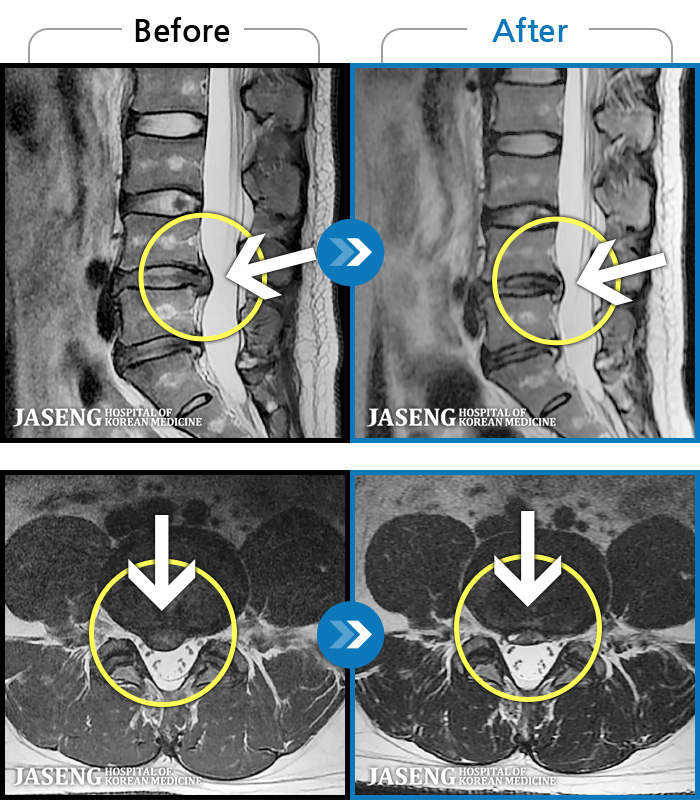

- MRI ġ

MRI ġ

1,304 MRI ũ ʸ Ȯϼ.